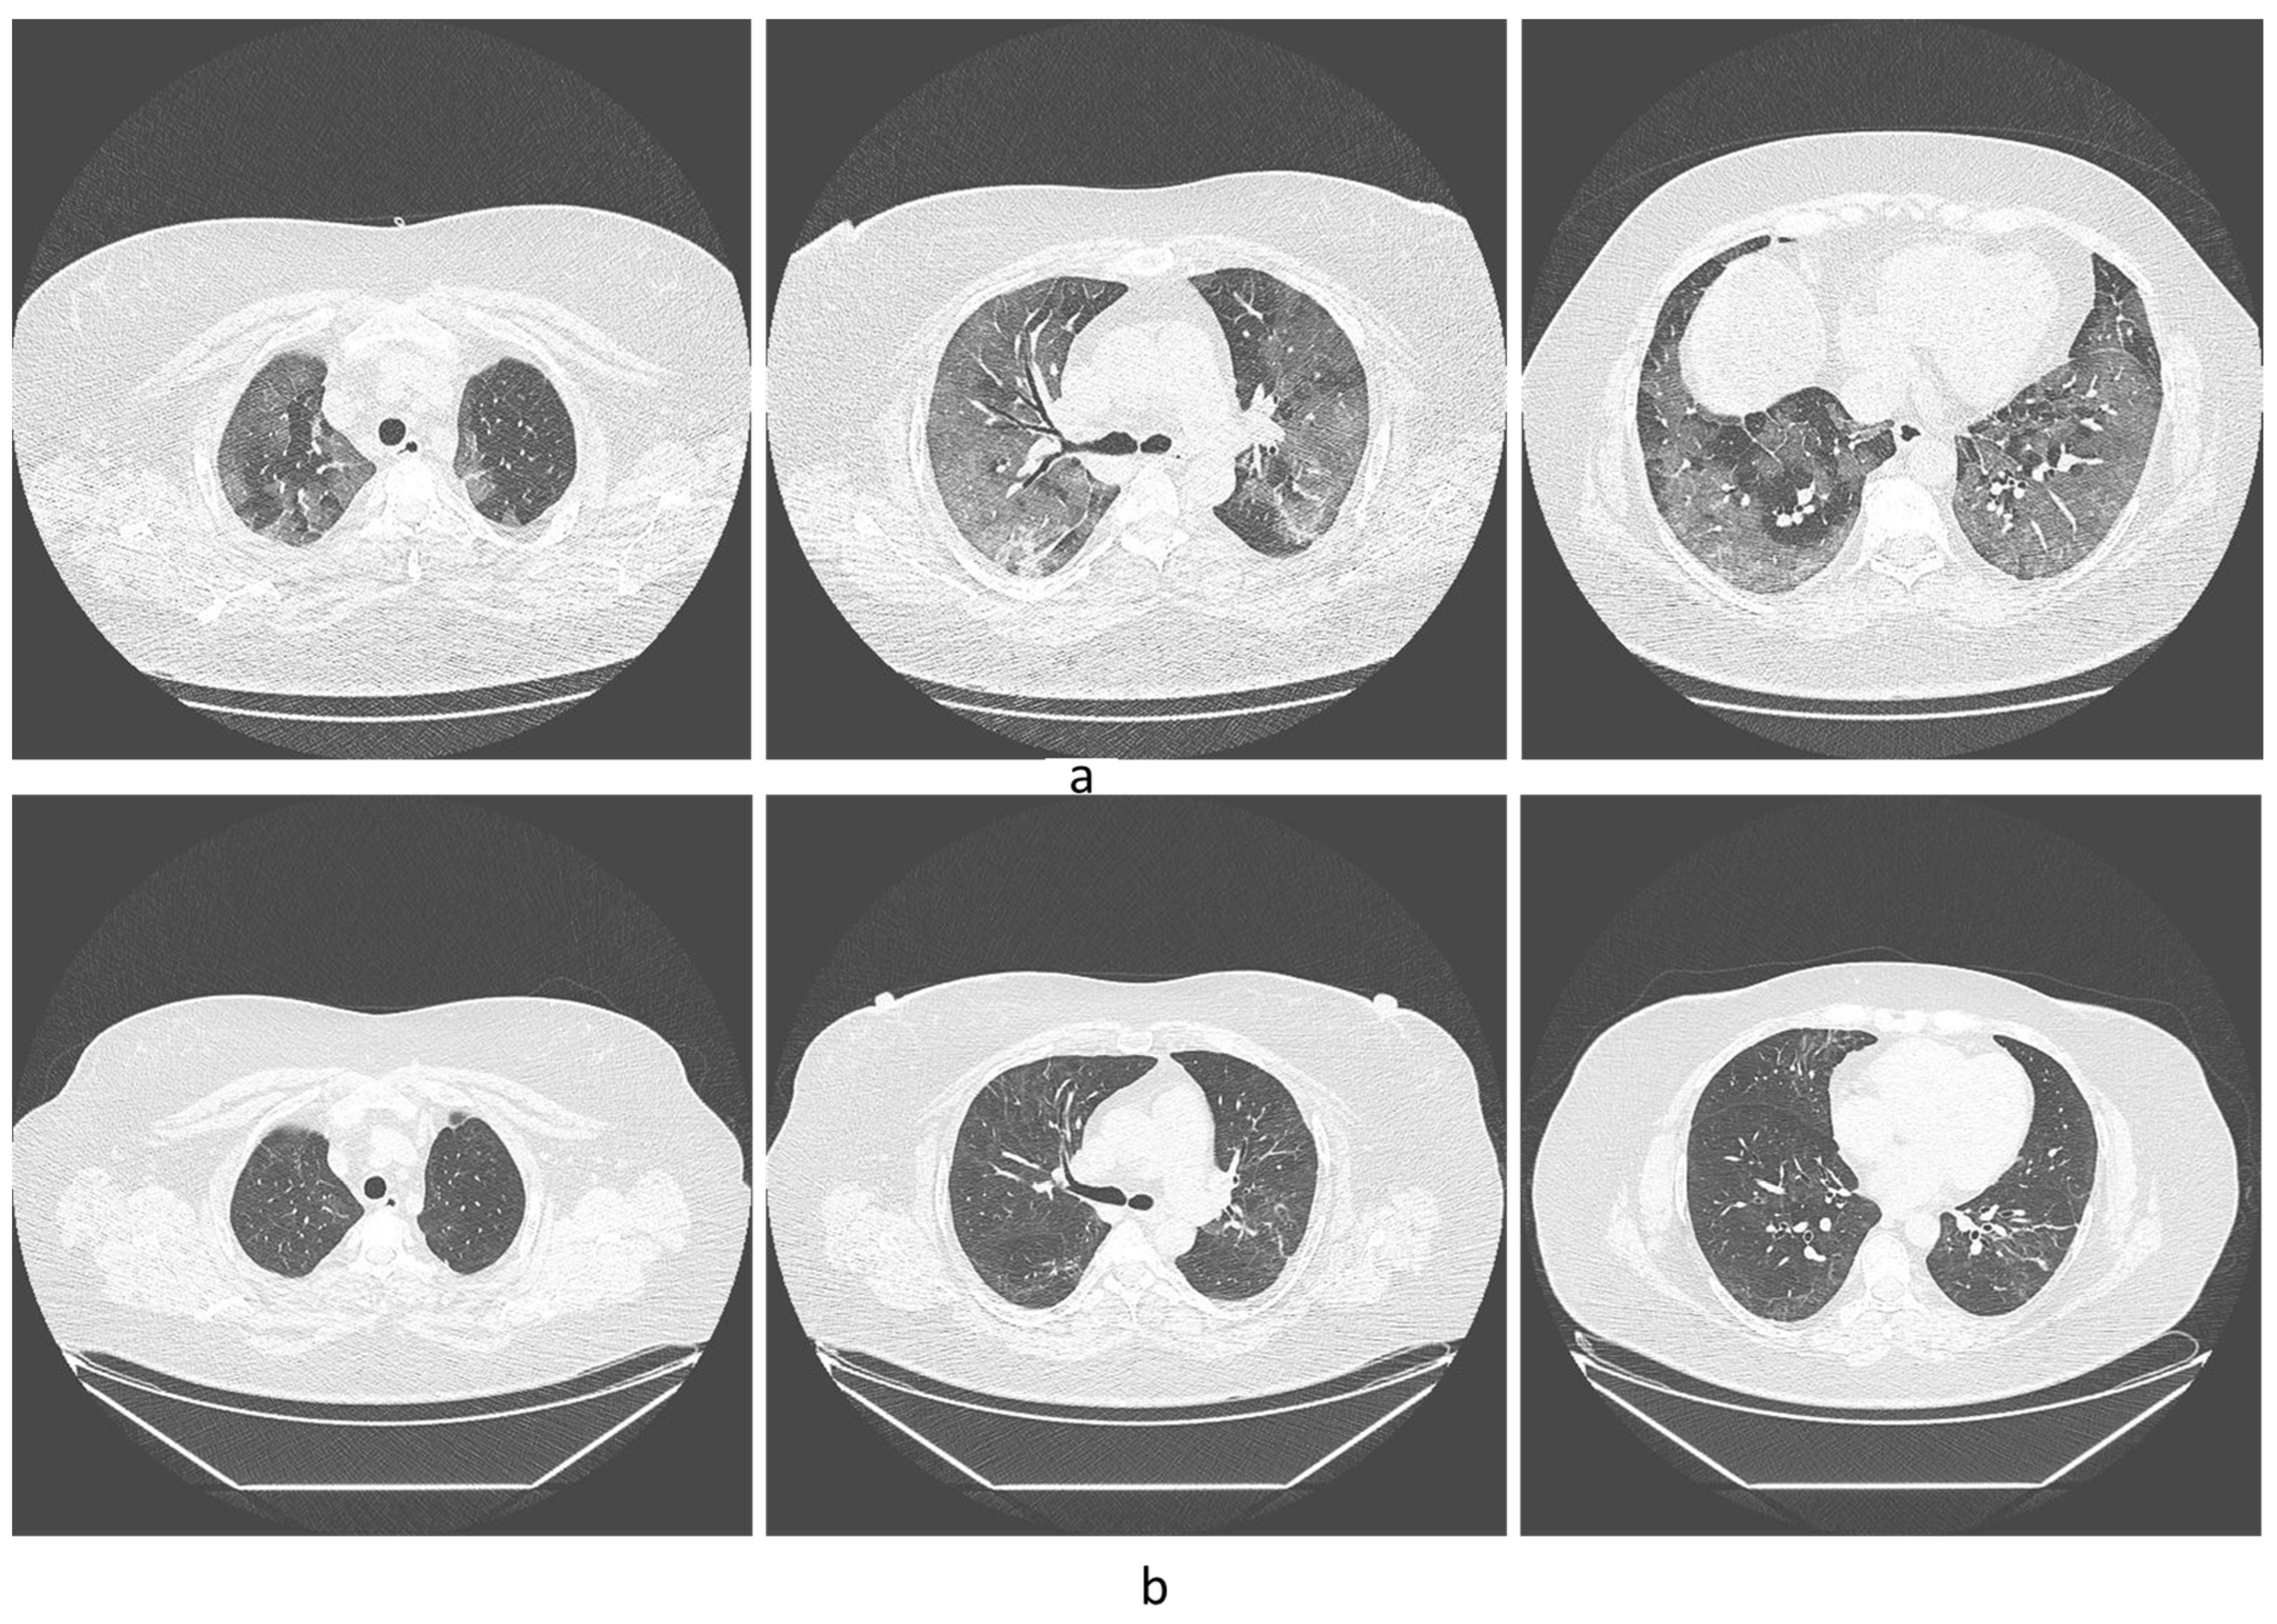

- Mogami, R.; Araújo Filho, R.C.; Chantong, C.; Gianella, C.; Santos de Almeida, F.C.; Baptista Koifman, A.C.; Jauregui, G.F.; Mafort, T.T.; da Silva Bessa da Costa, H.; Peres dos Santos, G.A.; et al. The Importance of Radiological Patterns and Small Airway Disease in Long-Term Follow-Up of Postacute COVID-19: A Preliminary Study. Radiol. Res. Pract. 2022, 2022, 7919033. [Google Scholar] [CrossRef]

- Kotzé, P.B.; Manthey, R.; Griffith-Richards, S.; Ackermann, C.; Klusmann, K. Computed tomography chest findings in post-acute COVID-19 lung disease at a South African regional hospital—A descriptive study. Pan Afr. Med. J. 2023, 44, 175. [Google Scholar] [CrossRef]

- Lehmann, A.; Gysan, M.; Bernitzky, D.; Bal, C.; Prosch, H.; Zehetmayer, S.; Milos, R.-I.; Vonbank, K.; Pohl, W.; Idzko, M. Comparison of pulmonary function test, diffusion capacity, blood gas analysis and CT scan in patients with and without persistent respiratory symptoms following COVID-19. BMC Pulm. Med. 2022, 22, 196. [Google Scholar] [CrossRef]

- Pan, F.; Yang, L.; Liang, B.; Ye, T.; Li, L.; Li, L.; Liu, D.; Wang, J.; Hesketh, R.L.; Zheng, C. Chest CT Patterns from Diagnosis to 1 Year of Follow-up in Patients with COVID-19. Radiology 2022, 302, 709–719. [Google Scholar] [CrossRef]

- Corsi, A.; Caroli, A.; Bonaffini, P.A.; Conti, C.; Arrigoni, A.; Mercanzin, E.; Imeri, G.; Anelli, M.; Balbi, M.; Pace, M. Structural and functional pulmonary assessment in severe COVID-19 survivors at 12 months after discharge. Tomography 2022, 8, 2588–2603. [Google Scholar] [CrossRef]

- Watanabe, A.; So, M.; Iwagami, M.; Fukunaga, K.; Takagi, H.; Kabata, H.; Kuno, T. One-year follow-up CT findings in COVID-19 patients: A systematic review and meta-analysis. Respirology 2022, 27, 605–616. [Google Scholar] [CrossRef]

- Lerum, T.V.; Meltzer, C.; Rodriguez, J.R.; Aaløkken, T.M.; Brønstad, E.; Aarli, B.B.; Aarberg-Lund, K.M.; Durheim, M.T.; Ashraf, H.; Einvik, G.; et al. A prospective study of pulmonary outcomes and chest computed tomography in the first year after COVID-19. ERJ Open Res. 2023, 9, 00575. [Google Scholar] [CrossRef]